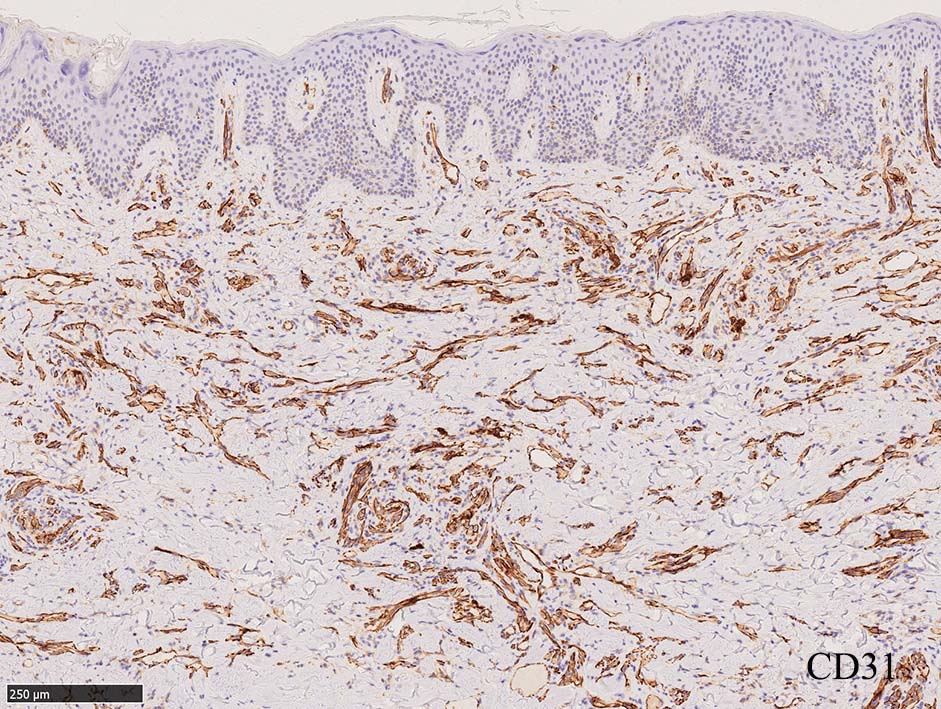

増生細胞はCD31, CD34, Factor Ⅷ, D2-40などが陽性を示す.

細血管周囲に血管内皮様の紡錘形細胞が増生, 一部に赤血球をいれた裂隙の形成がある. 細胞の異型はみられず, mitosisの増多もない. hemosiderin-laden macrophageが散在する.

病変は真皮内に現局している. 初期斑状病変に相当すると考えられる. 本例では, 特徴とされる形質細胞浸潤増加はみられない.